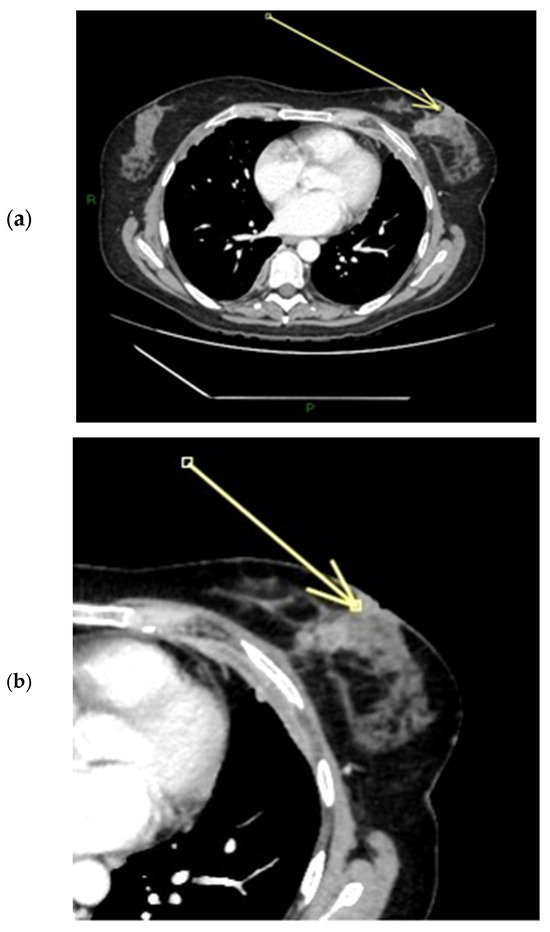

Figure 11.

(a–c) Patient’s name V.F. During ce-MR, we notice a flat thickened right nipple, with the representation of SLE, NEZ, and marked patchy INE pattern of enhancement (a). In the ce-T1 sequence (a) and in the MIP reconstruction (b), we can observe the presence of a partly necrotic mass-like enhancement of at least 6 cm located in the external quadrants of the right breast; the non-mass-like enhancement component that infiltrates the nipple measures approximately 3 cm and extends anteriorly to the gross mass (arrow in a). In the ce-CT scan, the arrow shows enhancement of both the base and the body of the right nipple. Morphology is flat, with skin thickening associated (c).

Figure 12.

(a–c) Patient’s name DN.A. The external quadrants of the right breast are occupied by a mass lesion with non-mass peripheral components, which infiltrates the nipple, retracting it. During ce-MR, we see a flat thickened right nipple, with SLE, NEZ, and marked patchy INE pattern of enhancement (arrows in a,b). In the ce-CT scan, the arrow shows enhancement of both the base and the body of the right nipple. Morphology is inverted, with skin thickening and ulceration (c).